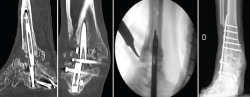

Figura 1. Imágenes radiográficas donde se observa rotura del clavo y extrusión del tornillo del astrágalo con ausencia de fusión. En la tercera imagen, proyección sagital de tomografía computarizada.

Se le realizó una ATTC mediante abordaje lateral transperoneal para el legrado de las articulaciones tibiotalar y subtalar, y fijación con un clavo tibiotalocalcáneo (TTC) retrógrado modelo Phoenix® (Zimmer Biomet) de 180 mm de longitud y diámetro de 11 mm. Ante el retraso de la consolidación, el clavo se dinamizó a los 6 meses de la implantación retirando el tornillo de bloqueo proximal. A los 15 meses se observó falta de fusión tanto de la articulación tibiotalar como subtalar y rotura del clavo con extrusión del tornillo de bloqueo del astrágalo (Figura 1).